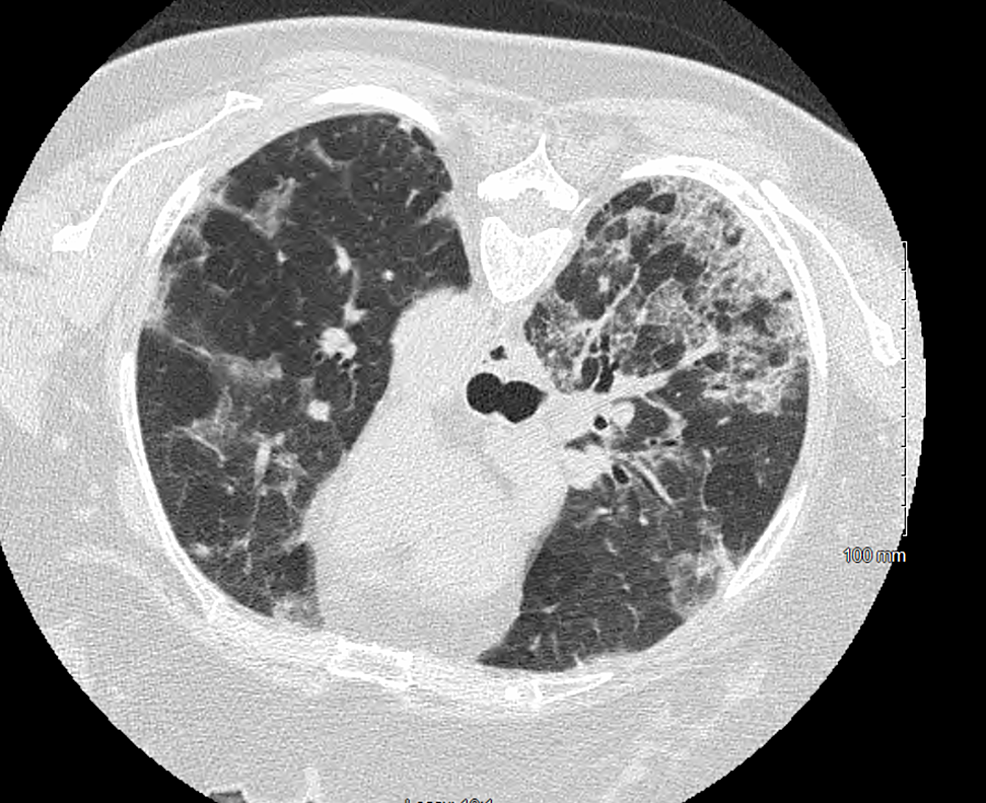

From www.ctchestreview.com

Case 74 Multifocal / Diffuse Pleural Disease Differential For Multifocal Pneumonia 37 the differential diagnosis includes alveolar proteinosis, infection (eg, pneumocystis jirovecii. Once again, there is a broad differential diagnosis for such findings. Consider this in three situations: (2) high risk for c. Involvement of a single lobe of the lung. (1) animal exposure (covers zoonotic pneumonias). Difficile infection (doxy reduces risk). Differential For Multifocal Pneumonia.